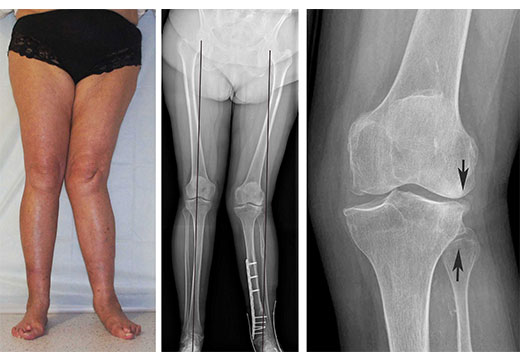

Особенность вальгусного искривления – изменение формы ног, при котором голени приобретают дугообразную форму и смыкаются у коленей (похоже на букву Х). Со временем ситуация усугубляется: ребенок опирается только на внутренние края подошвы, вследствие развивается плосковальгусная деформация и плоскостопие. Существует варусный тип деформации, при котором ноги напоминают букву О.

Чтобы верно подобрать тактику лечения, нужно предварительно провести диагностику. При подозрении на вальгусную деформацию назначается рентген, анализ крови, УЗИ. Дополнительно могут быть проведены плантография, подометрия (исследование ступни на предмет осложнений).